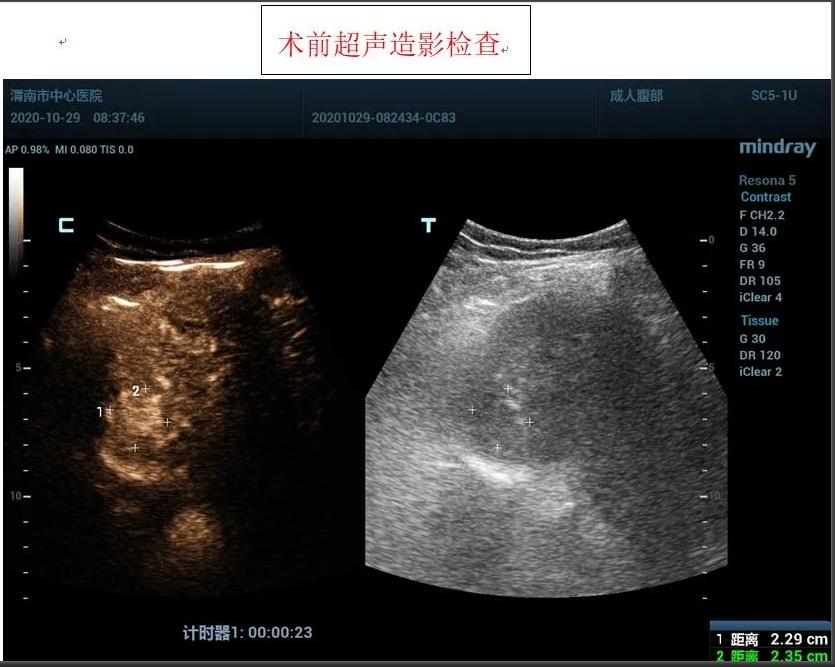

患者女性,71岁,因“糖尿病、肝硬化”在外院进行治疗,住院前进行常规检查,发现肝脏占位性病变,为进一步诊治前来我院,入住感染性疾病科,为进一步明确肝脏肿瘤性质,为患者进行超声造影检查,根据超声造影血流灌注情况,提示肝脏右前叶上段肝细胞癌可能。

患者肿瘤较小且位置较深,紧贴膈肌,且患者伴有冠心病、糖尿病等基础性疾病,感染科李红兵主任在充分评估患者状况后,与超声科刘晓晖主任进行细致讨论,决定对患者行超声引导下微波消融术,因病灶位置特殊,为减少手术风险,特邀西京医院王建宏教授前来进行指导,借助超声造影对肿瘤的部位和血供进行评估和确认后,华玺副主任医师在超声引导下穿刺取活检(病理结果为肝细胞癌)、布针、将消融针娴熟准确地刺入肿块,对肿块进行灭活治疗。

据超声科刘晓晖主任介绍,超声造影技术联合微波消融术可以在术前更明确的反映肿瘤病灶的实际大小及其浸润范围,可将微波治疗范围以超声造影测值作为参考,从而更客观的判断肿瘤病灶大小及周围浸润情况,确认需治疗的范围,同时可以使用超声造影在微波消融术中进行检测引导,术后通过超声造影确认肿瘤是否完全灭活。该方法与传统外科手术相比创伤小,手术时间短,术中痛苦小,并发症极少;术后恢复快,缩短了住院时间,乐鱼在线登录入口超声科将超声造影技术与微波消融术联合使用,为患者带来了新的治疗希望。